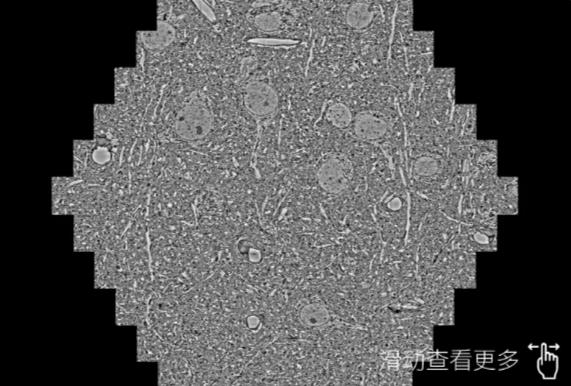

鼠脑切片。左图使用潮州蔡司潮州扫描电镜MultiSEM706对165μmx143pm面积区域成像,耗时仅需1.5秒。右图为鼠脑切片中30μm区域放大效果。样品由芝加哥大学B.Kasthuri提供。

使用蔡司高速潮州扫描电镜MultiSEM对1mm²人脑皮层组织进行高分辨成像,并对其中的各种细胞结构进行三维重构分析。左图展示了2x3mm²组织平面中锥体神经元的三维重构效果。右图显示了局部体积神经元三维重构。图像由哈佛大学chtman实验室提供,渲染图由D. Berger 制作。